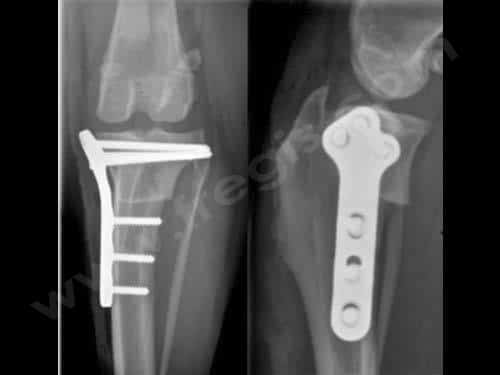

L’ostéotomie ainsi réalisée est stabilisée au moyen d’une plaque très spécifique et de vis osseuses. Ces implants, s’ils ne posent pas de problèmes au chien opéré, peuvent être laissés en place, à vie après la consolidation osseuse.